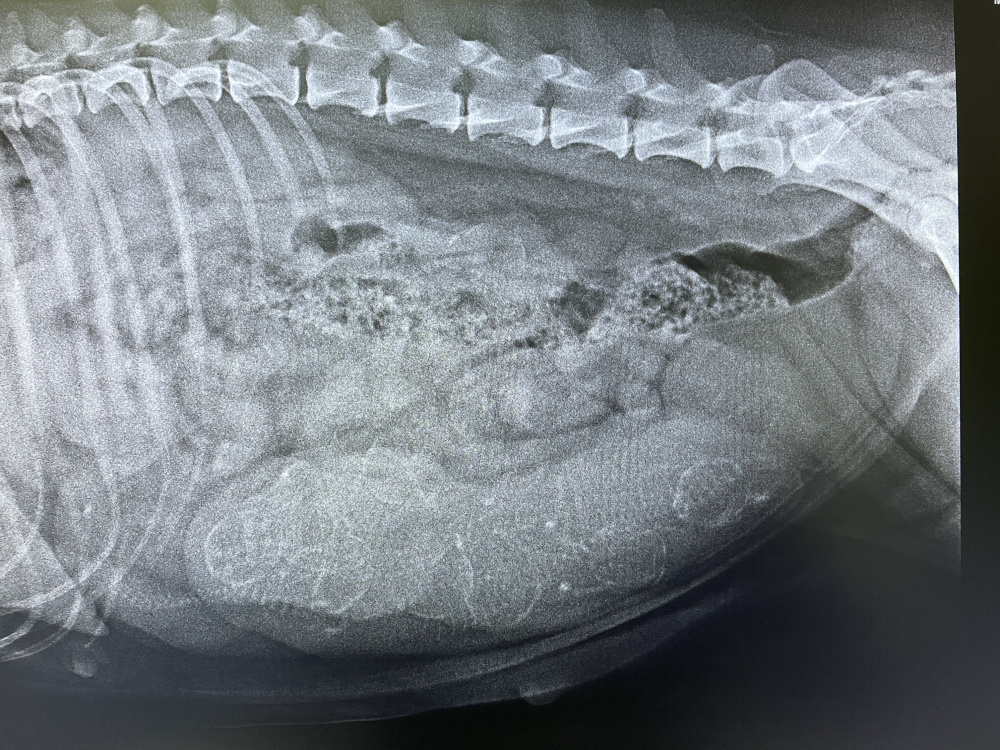

10 Tage noch bis zum errechneten Wurftermin, die letzte Untersuchung beim Tierarzt. Es wird ein Röntgenbild angefertigt um zu schauen, wieviele Welpen Emma in sich trägt. Vielleicht hätten wir noch ein paar Tage warten sollen, jedenfalls lässt es sich nicht ganz genau erkennen. Der Tierarzt zählt 5 - 6 Welpen.